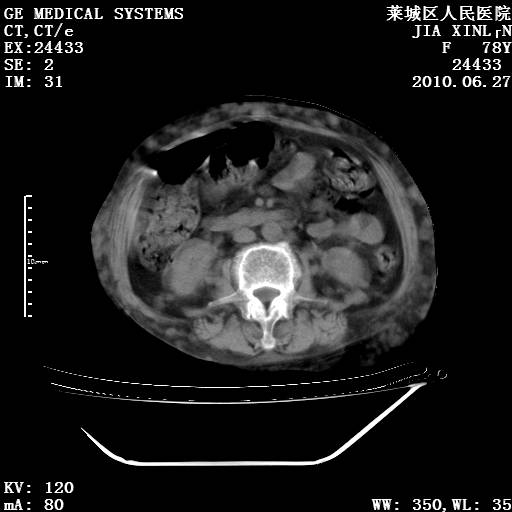

以下是引用胡宇在2010-7-2 19:11:00的发言:[br]神经纤维瘤的特点为:肿块呈多发性、数目不定,少的几个,多的可成百上千难以计数。小的如米粒,大的似拳头,甚至可达十数公斤以上。可松弛地悬挂于皮表,皱褶及松弛可致畸形明显。神经纤维瘤沿神经干的走向生长时呈念珠状,或蚯蚓块状形结节。此外神经纤维瘤皮肤可出现咖啡斑,大小不一,形如雀斑小点状,或大片状,分布与神经纤维瘤肿块的分布无关。肿瘤数目不多的患者,皮肤色素咖啡斑状沉着是纤维神经瘤的重要诊断之一。 本病多发于躯干,有时出现于四肢及面部,患者常合并许多疾病应予重视加以区别。 [br] [br] [br] [br]lyb999说 [br]